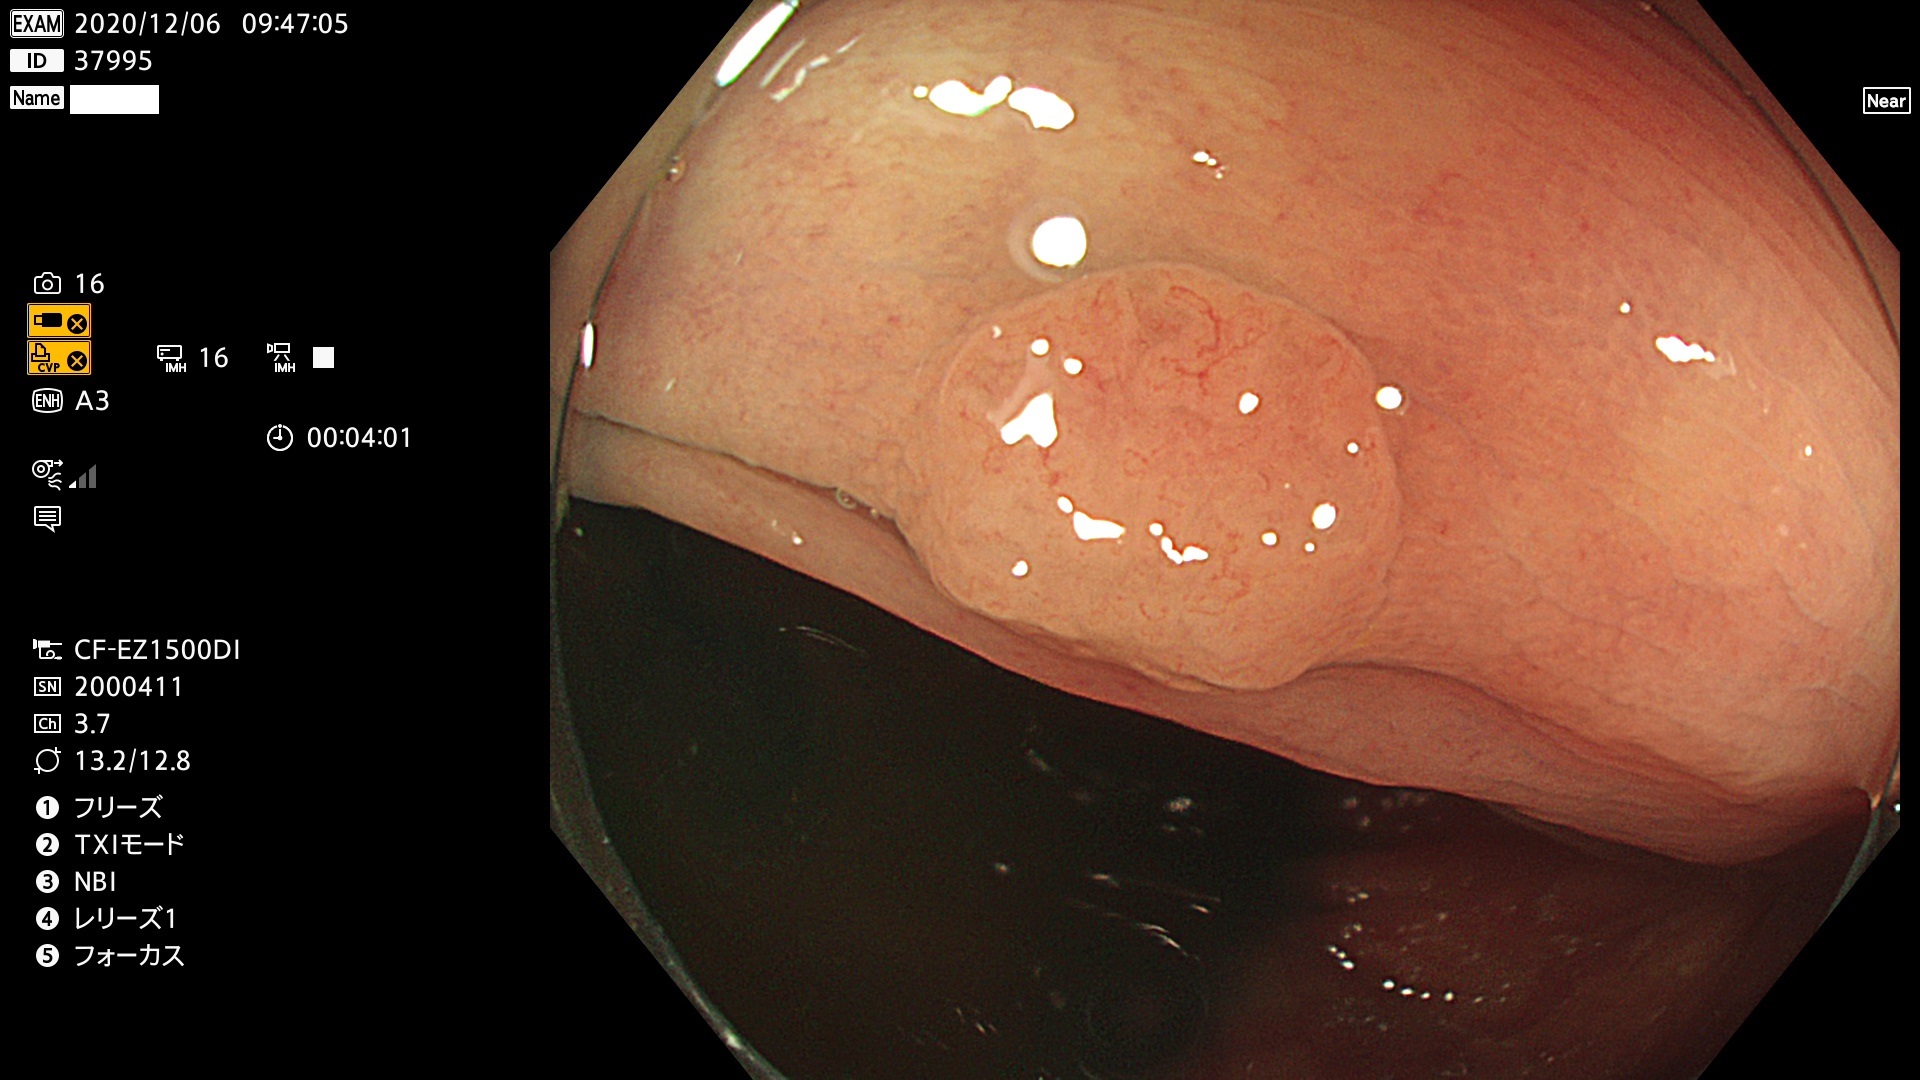

37900 37902 37903 37904 37905 37906 37907 37909 37910 37911 37912 37913 37914 37915 37916 37917 37919 37921 37922 37923 37926 37928 37929 37930 37931 37933 37934 37935 37936 37937 37938(SSAPのみ) 37939 37940 37941 37942 37943 37946 37947 37948 37949 37951 37952 37953(SSAPのみ) 37955 37956 37957(SSAPのみ) 37958(SSAPのみ) 37960 37962 37963 37964 37966 37967 37968 37971 37972 37973 37975 37976 37977 37979 37982 37983 37984 37985 37986 37987 37988 37989 37990 37991 37992 37993 37994 37995 37996 37998 37999

発見困難で危険性の高い平坦型病変(上記100名より抽出)